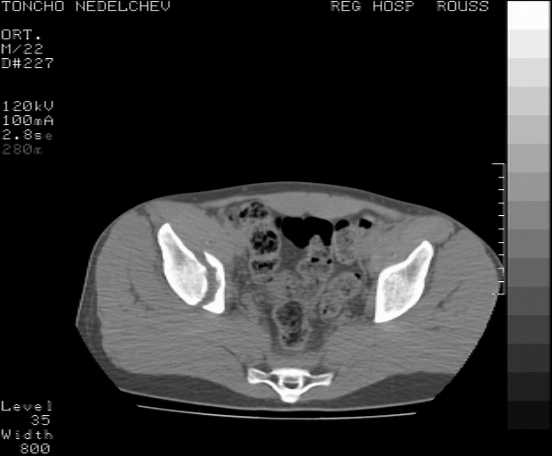

The details of the fracture are not so clear from the images sent...would you be able to send along an AP and Judet images as well as some additional axial images above and below the joint?

I’m not so sure that your patient has a Tr+PW pattern based on the images sent...maybe the fracture’s exact name won’t matter in the long run, but it’d be great to see enough images to make an accurate comment.

Here are some more axial images. What is your opinion as for the timing of the operative treatment?